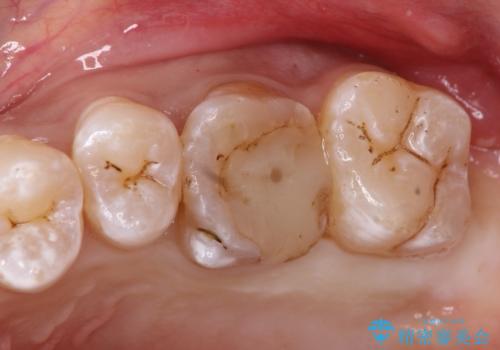

検査で見つかった虫歯 セラミッククラウンでの治療

担当医 岡田康成